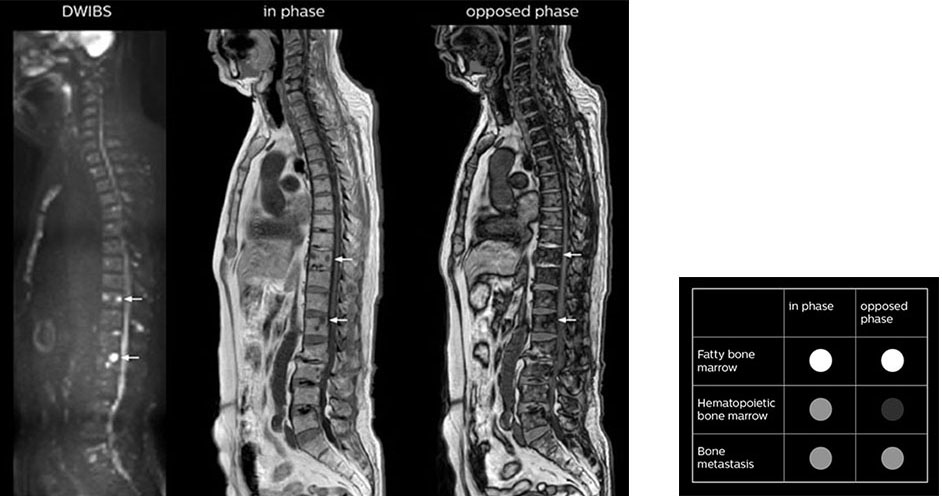

“mDIXON FFE allows us to quickly get information we need to assess the presence of fat. That gives us more information when we need to diagnose bone lesions, and when we are asked to judge fat-containing lesions such as hepatocellular or renal carcinoma,” Dr. Nobusawa says.

“The mDIXON fat images can help us to differentiate fatty bone marrow from bone lesions. This is especially useful in elderly people, who tend to have fattier bone marrow. The water images provide a high signal-to-noise ratio in the intestinal canal, which is valuable for visualizing lesions in the colon,” he says.

“In-phase and out-phase sagittal T1-weighted FFE images help us to visualize and further characterize bone lesions such as metastasis and bone-marrow hyperplasia that have high signal on DWI. These images are also used throughout radiotherapy, to monitor changes in the fatty bone marrow.”